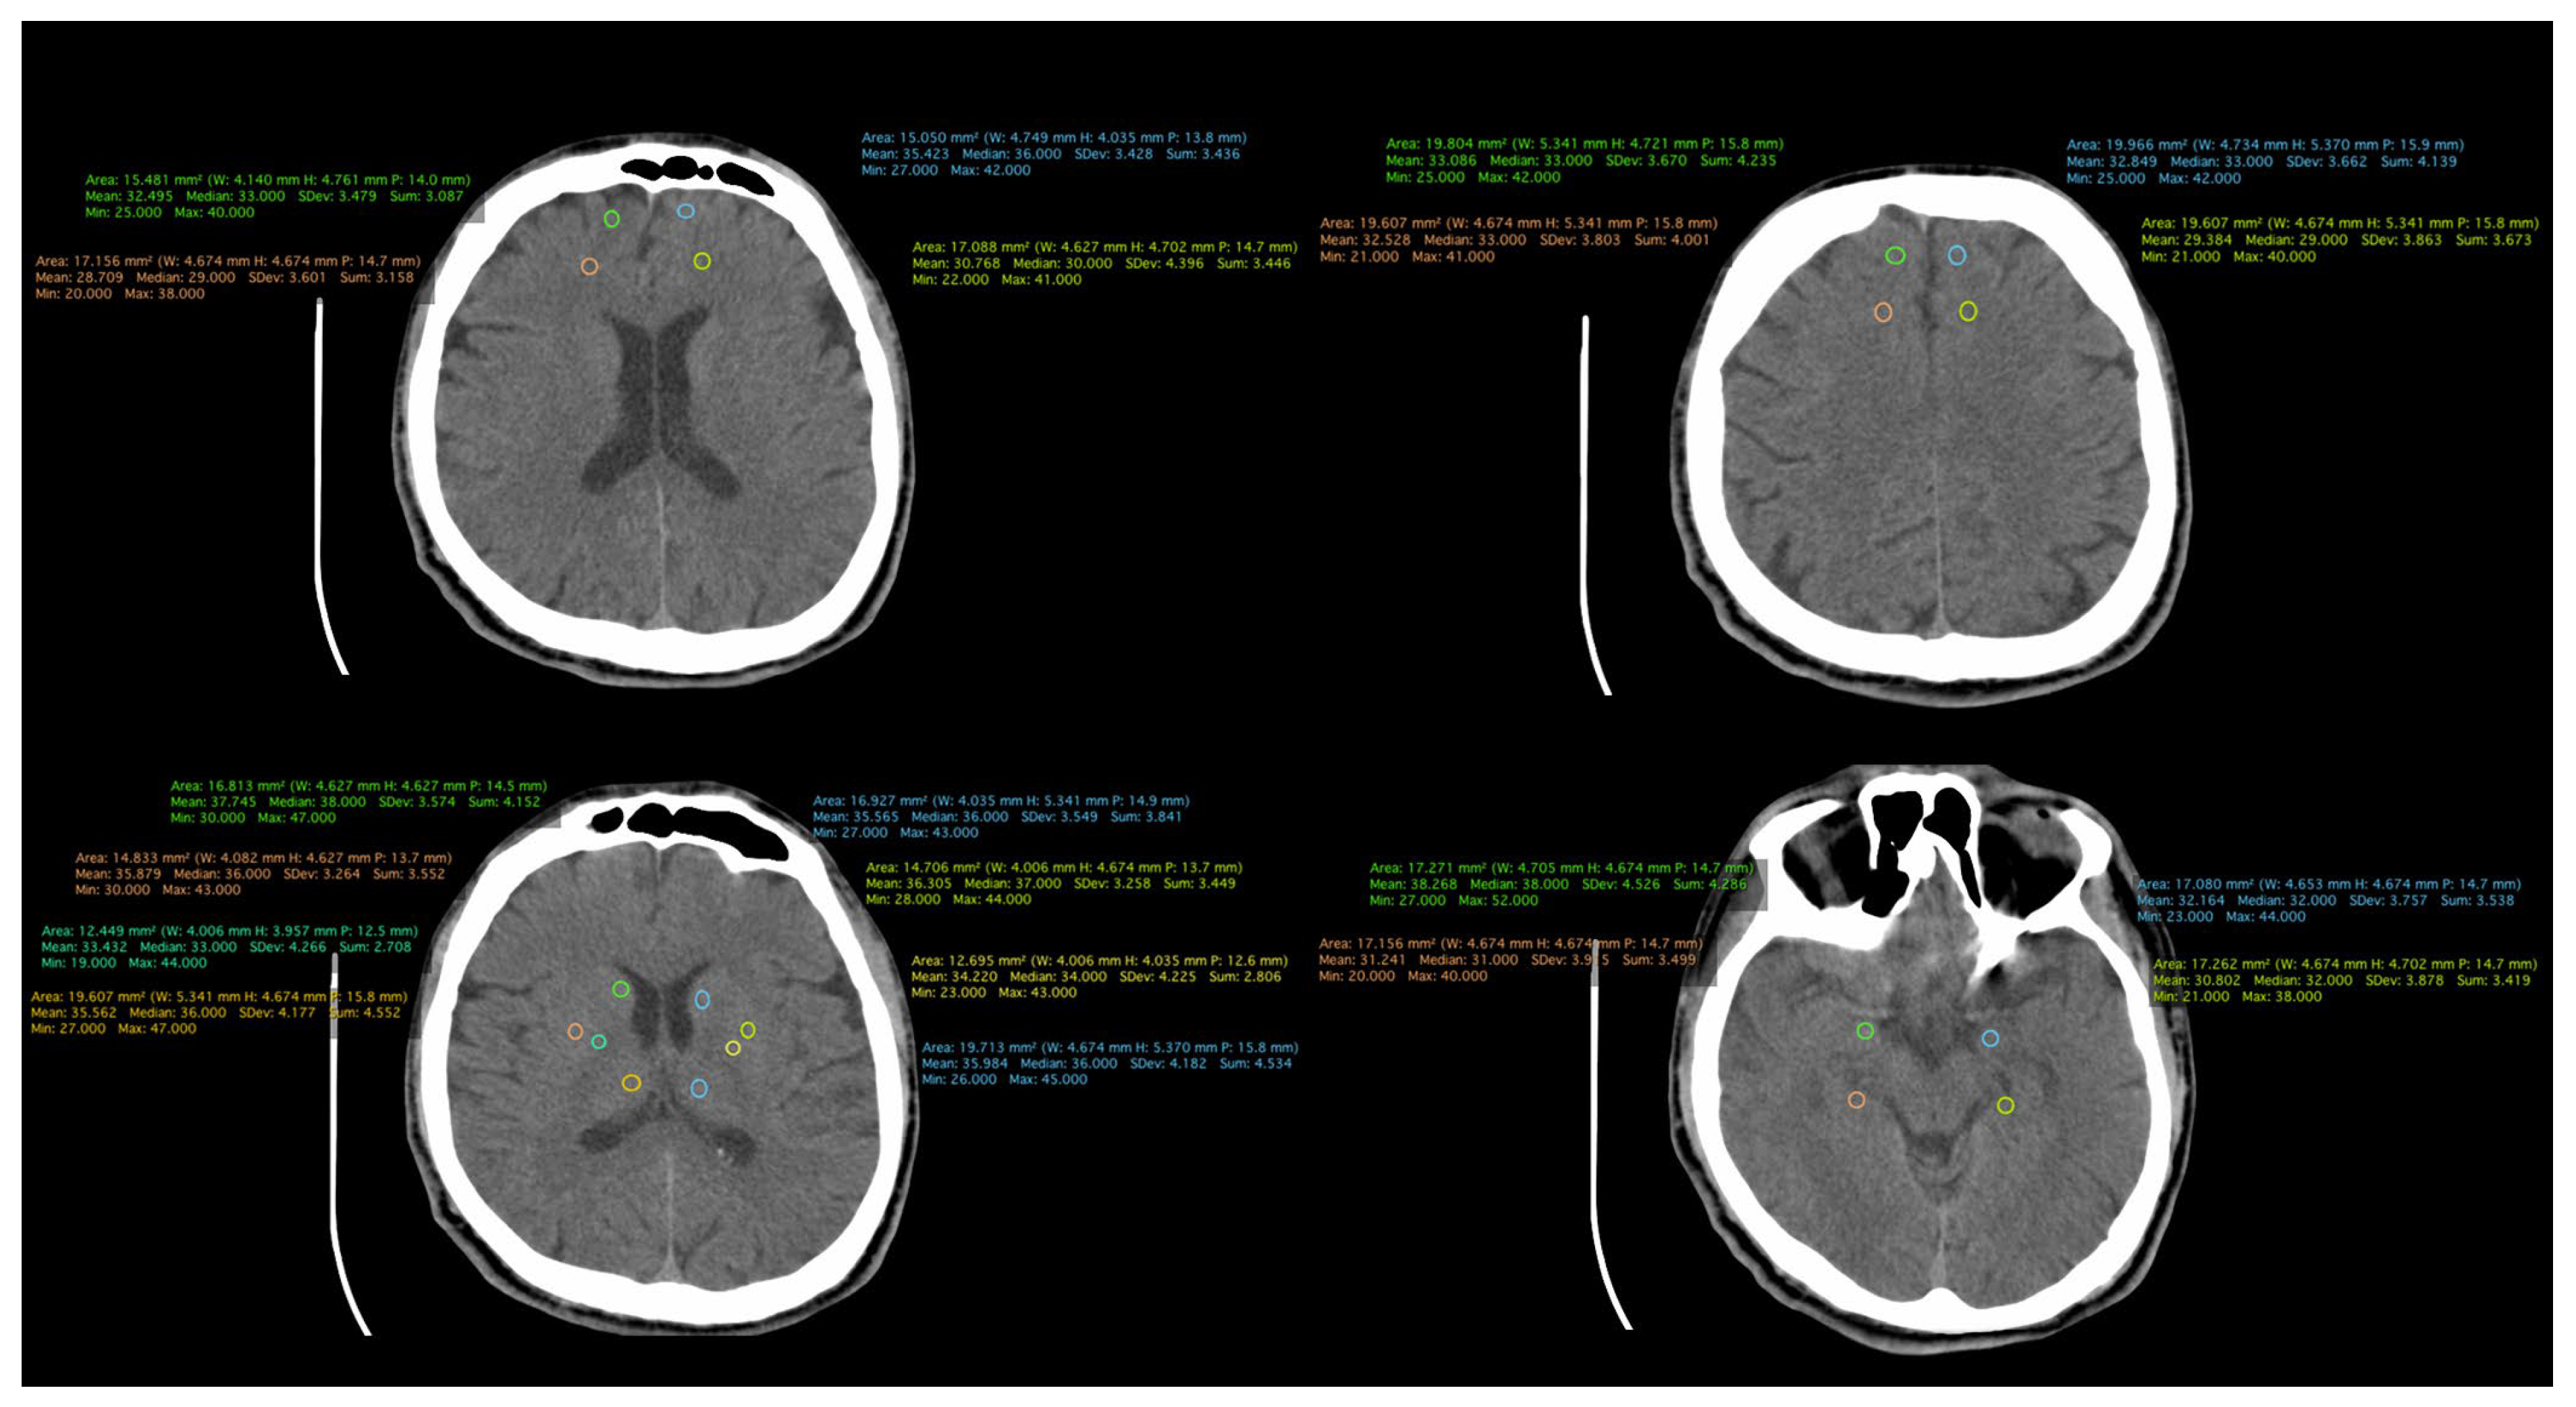

All patient-related information was collected from the paper and electronic patient records. Data were collected by certified medical staff, including board-certified psychiatrists and an imaging specialist. The database included demographic data, information regarding the onset and duration of the illness, the number of episodes, and the type of treatment received. Additionally, information obtained through CT examinations was incorporated, including measurements such as the transverse diameter between the frontal horn tips on axial section, transverse diameter at the level of the lateral ventricle bifurcation at the most cranial point of the ventricle on axial section, transverse diameter at the level of the diencephalic third ventricle on axial section, antero-posterior diameter at the level of the fourth ventricle on axial section, and density measurements in both the anterior and posterior portions of the frontal lobe at the cortical and subcortical levels. (Figure 1, Figure 2 and Figure 3).

Figure 2. CT scan of a patient from the schizophrenia group.

The densities of structures in the frontal lobe were measured using cerebral CT explorations. In the cortical region, a higher density is evident in both the anterior right and left portions, as well as in the posterior right portion, in patients with schizophrenia compared to those in the first episode of the illness and those in the control group. As per the cortical area of the left posterior region, the highest density is observed in patients in the FES group. Notably, in the subcortical portion, a higher density is recorded in the anterior left region of the frontal lobe in schizophrenia patients, with the highest densities observed across all other regions in the FES group. The lowest densities across all measured structures were consistently found in the control group (Figure 6). The statistical analysis using the ANOVA test for each structure individually is described in Table 2.